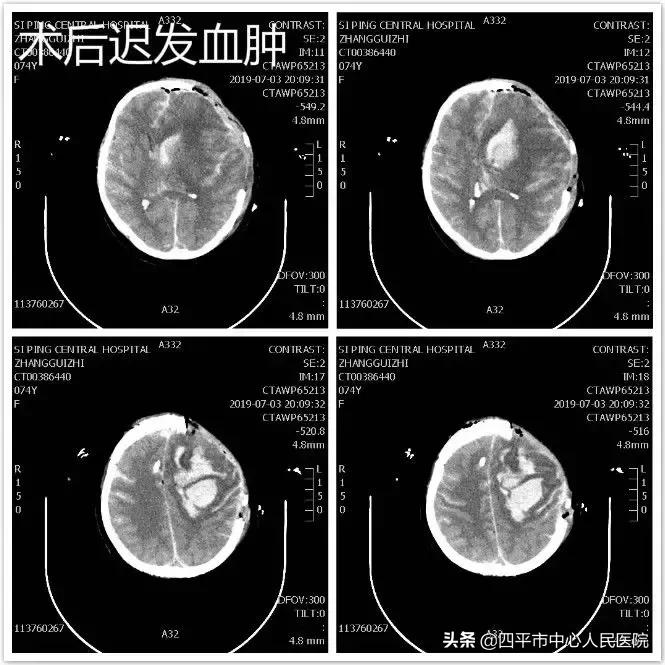

患者张XX,于入院前2小时突发神志不清,伴恶心呕吐,呕吐物为胃内容物,四肢不动,伴尿*禁失**,无抽搐。由家属送至梨树县医院,行头CT检查提示脑出血,为求进一步治疗转送至我院,我院神经内科给予复查头CT提示大量蛛网膜下腔出血,首先颅内动脉瘤破裂所致,由于患者到我院时深度昏迷状态,呼吸微弱,HUNT-HESS分级5级,不适合行头部CTA检查及介入栓塞治疗,家属强烈要求手术治疗,请麻醉科行气管插管后入手术室,李晓东主任带领马龙急诊全麻下经左侧扩大翼点入路行右侧脑室外引流术及颅内动脉瘤探查术,术中探查患者左侧后交通动脉巨大瘤,临时阻断颈内动脉后给予确切夹闭,术中动脉瘤没再次有破裂出血。术后第1天,患者呈浅昏迷状态,刺痛可定位,四肢可自主活动。复查头部CT满意,查头部CTA见左侧后交通动脉瘤夹闭确切。但患者于术后第3天,出现迟发性脑内血肿,考虑到预后不好,家属放弃治疗出院,临出院时对我科李晓东主任及马龙医生的积极救治表示感谢。